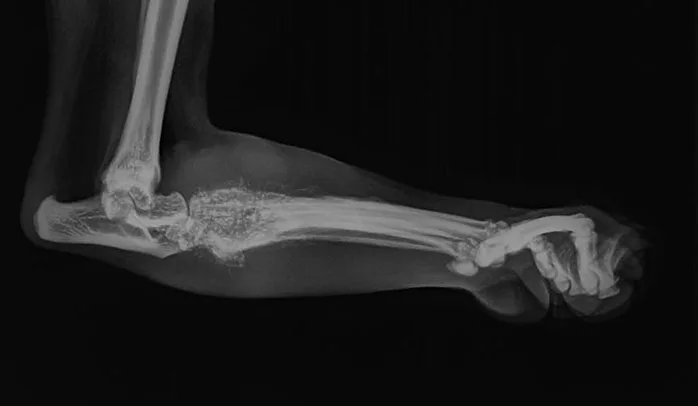

Radiographs of the left proximal metatarsal/tarsal region revealed multiple foci of osteolysis within the distal tarsal and proximal metatarsal bones, as well as marked soft tissue swelling of the area (Figure 1). Periosteal reaction was noted on the dorsal and plantar surfaces of the distal tarsal and proximal metatarsal bones.

Figure 1

Multiple foci of osteolysis and surrounding marked soft tissue swelling in the distal tarsal and proximal metatarsal bones